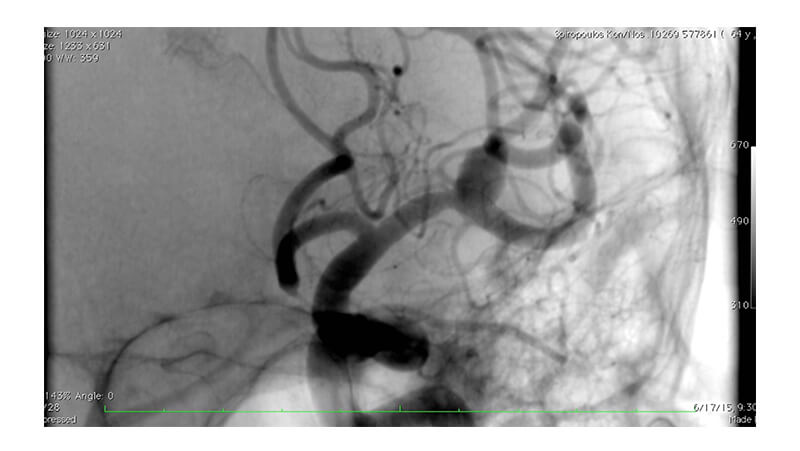

Εικόνα 3, 4: Τοποθέτηση flow diverter stent έμπροσθεν του αυχένα του ανευρύσματος (Pipeline, eV3).

Βλέπουμε την αποκατάσταση της στενώσεως του Μ1 τμήματος.